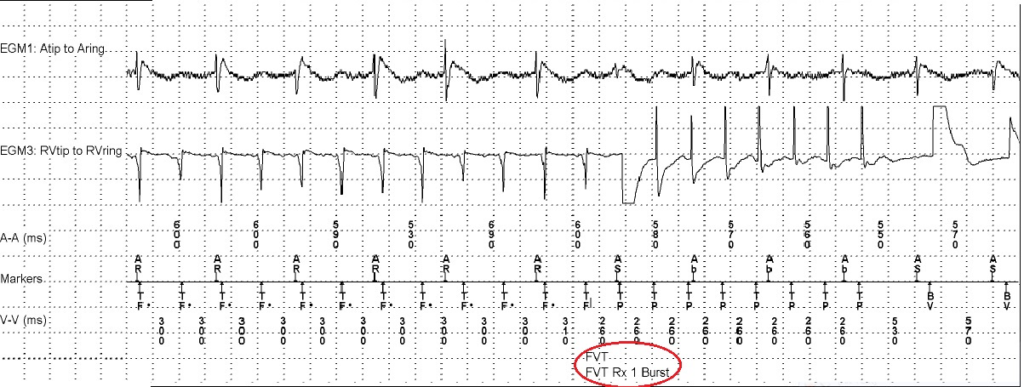

Een 78-jarige man met aanvallen van duizeligheid en hartjagen. Wat ziet u op het elektrogram (EGM)?

Antitachycardiepacing (ATP) middels burst ivm ventrikeltachycardie. De therapie is succesvol.

De cijfers die zijn afgebeeld betreffen cycluslengten in milliseconden. U rekent deze om naar slagen per minuut (/min) door 60.000 te delen door de cycluslengte. Bijvoorbeeld: 60.000/300 ms = 200/min

AR = boezem refractair

AS = boezem sensing

Ab = atriale blanking

TF = tachycardie gedetecteerd in FVT zone

TP = anti tachycardie pacing